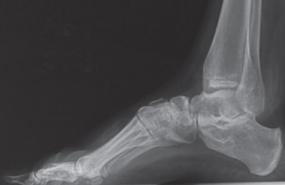

La responsable de la Clínica Grimalt Llinàs explica que es una deformidad del primer radio.